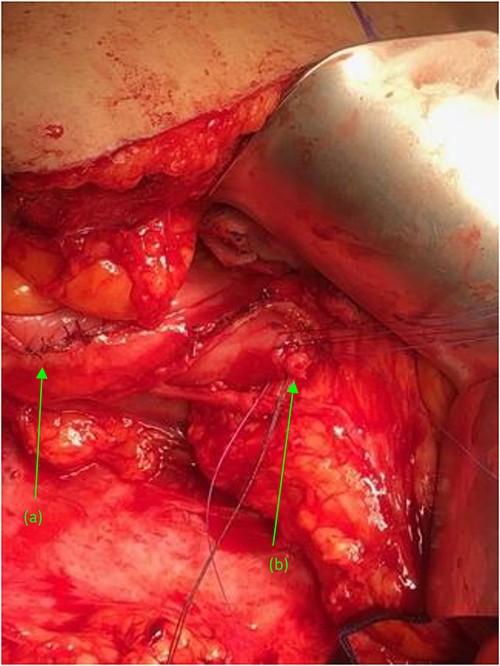

Attention was turned back to the fistulous connections at their duodenal entry points (Fig. 4). Both fistulas, were trimmed to their base, debrided, and primarily closed using 3-0 Vicryl sutures in an interrupted fashion. Interrupted 3-0 Vicryl sutures were then used to Lambert the repaired 2nd and 3rd portions of the duodenum (Fig. 5). Acti-seal sealant was sprayed atop the repairs, and Gerota’s was laid atop. Surgicel was then placed in the raw, inflamed posterior space of the fossa and adequate hemostasis was achieved. A 19 French Blake drain was brought through an inferior skin incision, laid in the renal fossa adjacent to the duodenal repairs, and sutured in place. The abdomen was then closed in the standard fashion, with individual suture closure of the fascia, internal and external oblique muscles and skin layers.

Two suture tagged fistulas status post fistulectomy and debridement to their base, entering the (a) second and (b) third portions of the duodenum, status post nephrectomy.